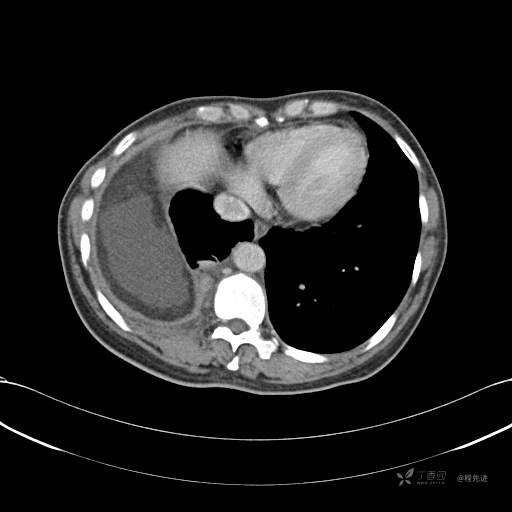

患者性别:女

患者年龄:51岁

简要病史:胸闷半年